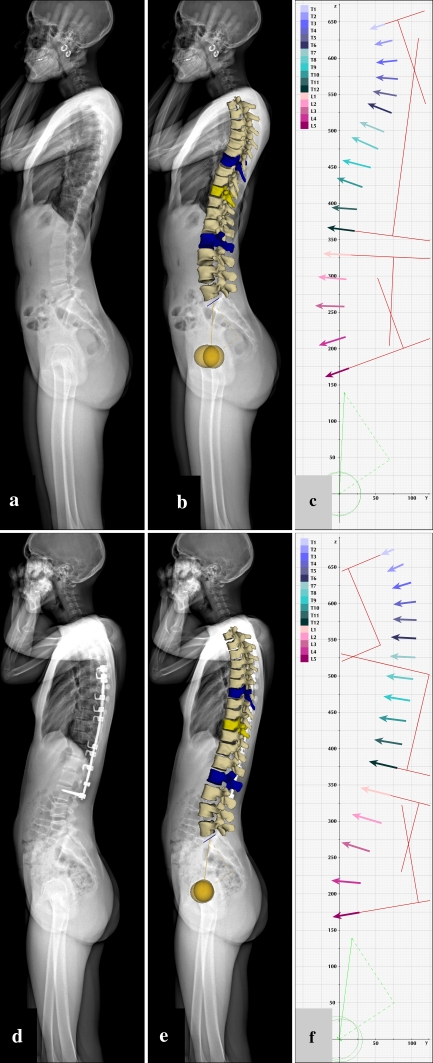

Surface 3D reconstructions of the spine by sterEOS 3D software based on the pre- and post-operative EOS X-ray images strictly followed the guidelines of the manufacturer. For a quantitative description of the scoliotic curves in the coronal and sagittal planes, the Cobb’s method was used. Sagittal curves were measured between vertebrae Th4 and Th12 for thoracic kyphosis and vertebrae LI and LV for lumbar lordosis. Instead of measurement of the angulation between lines corresponding to the upper and lower endplates of relevant vertebrae, the angles between the coronal and sagittal projections of a plane defined by the interpedicular axis and the vertebra vector of the corresponding vertebrae were used, i.e., the upper and lower-end vertebrae of the scoliotic curve for the coronal plane (Fig. 2c, f), and vertebrae Th4–Th12 (for thoracic kyphosis) and LI–LV (for lumbar lordosis) in the sagittal plane (Fig. 3c, f).

Fig. 2.

Coronal plane visualizations of the scoliotic spine (a–c) before and (d–f) after correction. Pre-operative and post-operative EOS X-ray images (a, d); images corresponding to pre-operative and post-operative sterEOS 3D reconstructions (b, e); and pre-operative and post-operative full spine vertebra vectors (c, f). Conventional Cobb angulation measurements (shown with red lines) are carried out using lines connecting pedicular centroids as detailed in “Methods”. See Table 1 for measurement values

Fig. 3.

Sagittal plane visualizations of the scoliotic spine (a–c) before and (d–f) after correction. Pre-operative and post-operative EOS X-ray images (a, d); images corresponding to pre-operative and post-operative sterEOS 3D reconstructions (b, e); and pre-operative and post-operative full spine vertebra vectors (c, f). Conventional Cobb angulation measurements (shown with red lines) are carried out using vertebra vectors as detailed in “Methods”. See Table 1 for measurement values

The patient presented a typical right convex major thoracic curve (Lenke type 1A) between vertebra Th7 and LII, with apical vertebra Th10. Corrective surgery was performed with posterolateral fusion between vertebra Th5 and LIII. Pre- and post-operative EOS X-ray images, images of sterEOS 3D surface reconstructions and full spine vertebra vectors in the frontal and sagittal plane views are shown in Figs. 2 and 3, respectively. Pre- and post-operative EOS 3D reconstructions and vertebra vectors for the full spine in the horizontal plane view are depicted in Fig. 4. Corresponding angulation measurement values and vertebra vector coordinate and parameter values are shown in Tables 1 and 2, respectively.